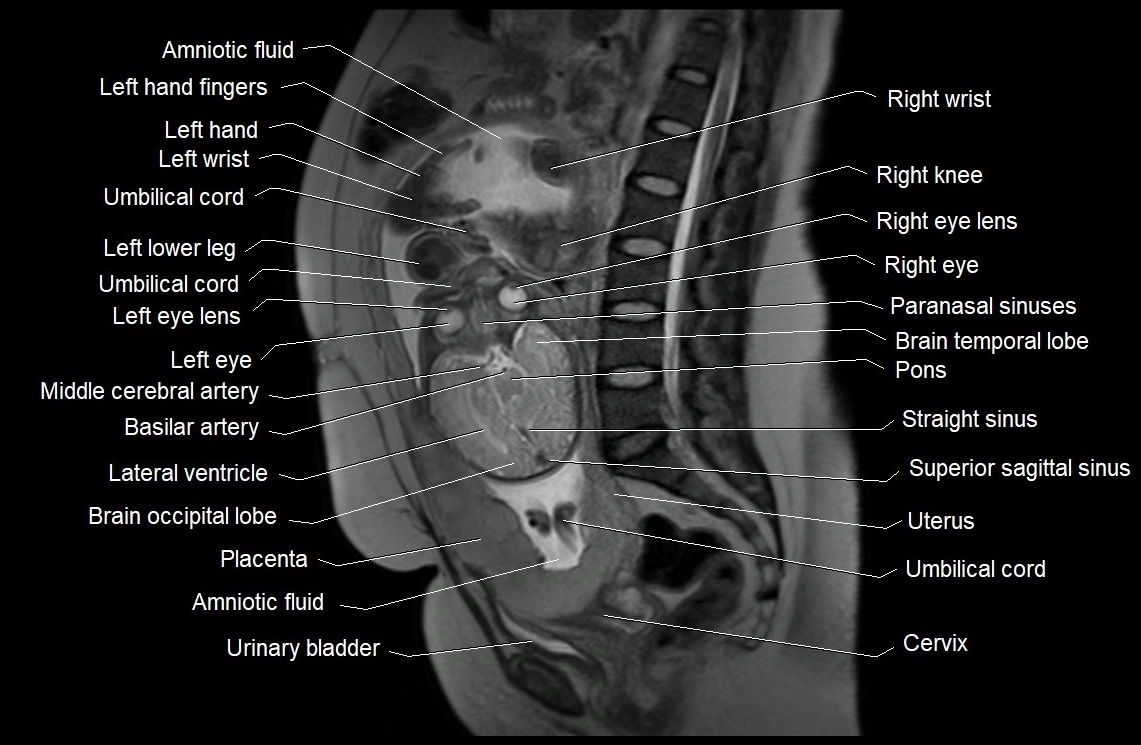

MRI Appearance

T2 HASTE (T2 GRE):

• Amniotic fluid shows very bright hyperintense signal

• Provides natural contrast against fetus and placenta

• Small particles (vernix) may appear as scattered hypointense foci within bright fluid